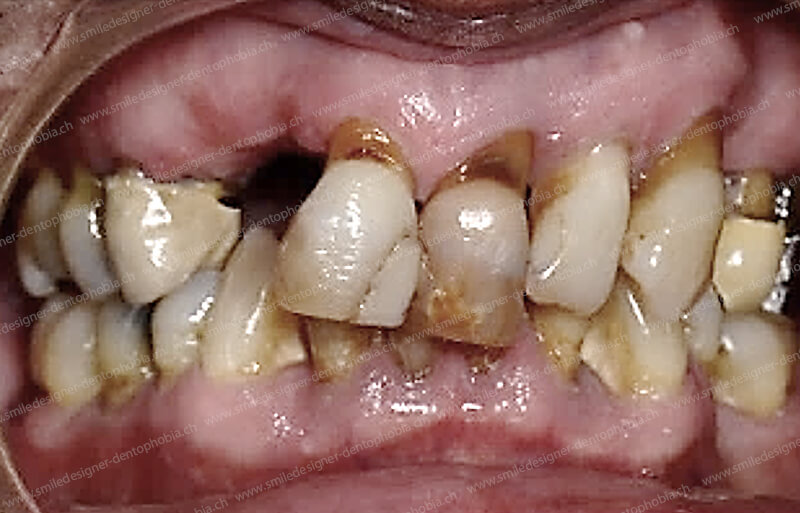

Cas clinique « GOLD STANDARD MCI » mandibulaire : Bridge implanto-porté sans extension postérieure (ALL ON 8). Version définitive du bridge avec un cosmétique en céramique.

traitement

Cas clinique « DAMAGE CONTROL MCI » mandibulaire : Bridge implanto-porté avec extensions postérieures (ALL ON 6). Version définitive du bridge avec un cosmétique en céramique.

Cas clinique « DAMAGE CONTROL MCI » mandibulaire : Bridge implanto-porté avec extensions postérieures (ALL ON 8). Version définitive du bridge avec un cosmétique en céramique.